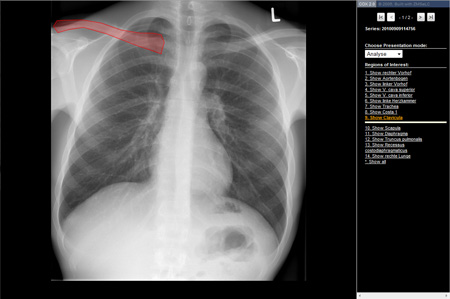

Abb. 1 „Analyse“: Rö-Thorax mit Markierung der anatomischen Strukturen

Der Modus „Analyse“ ermöglicht eine schnelle Übersicht der einzelnen für das aufgerufene Bild wichtigen anatomischen Strukturen. Es sind die Umrisse der jeweils ausgewählten Struktur mit Angabe der genauen Bezeichnung zu sehen (siehe Abb.1).